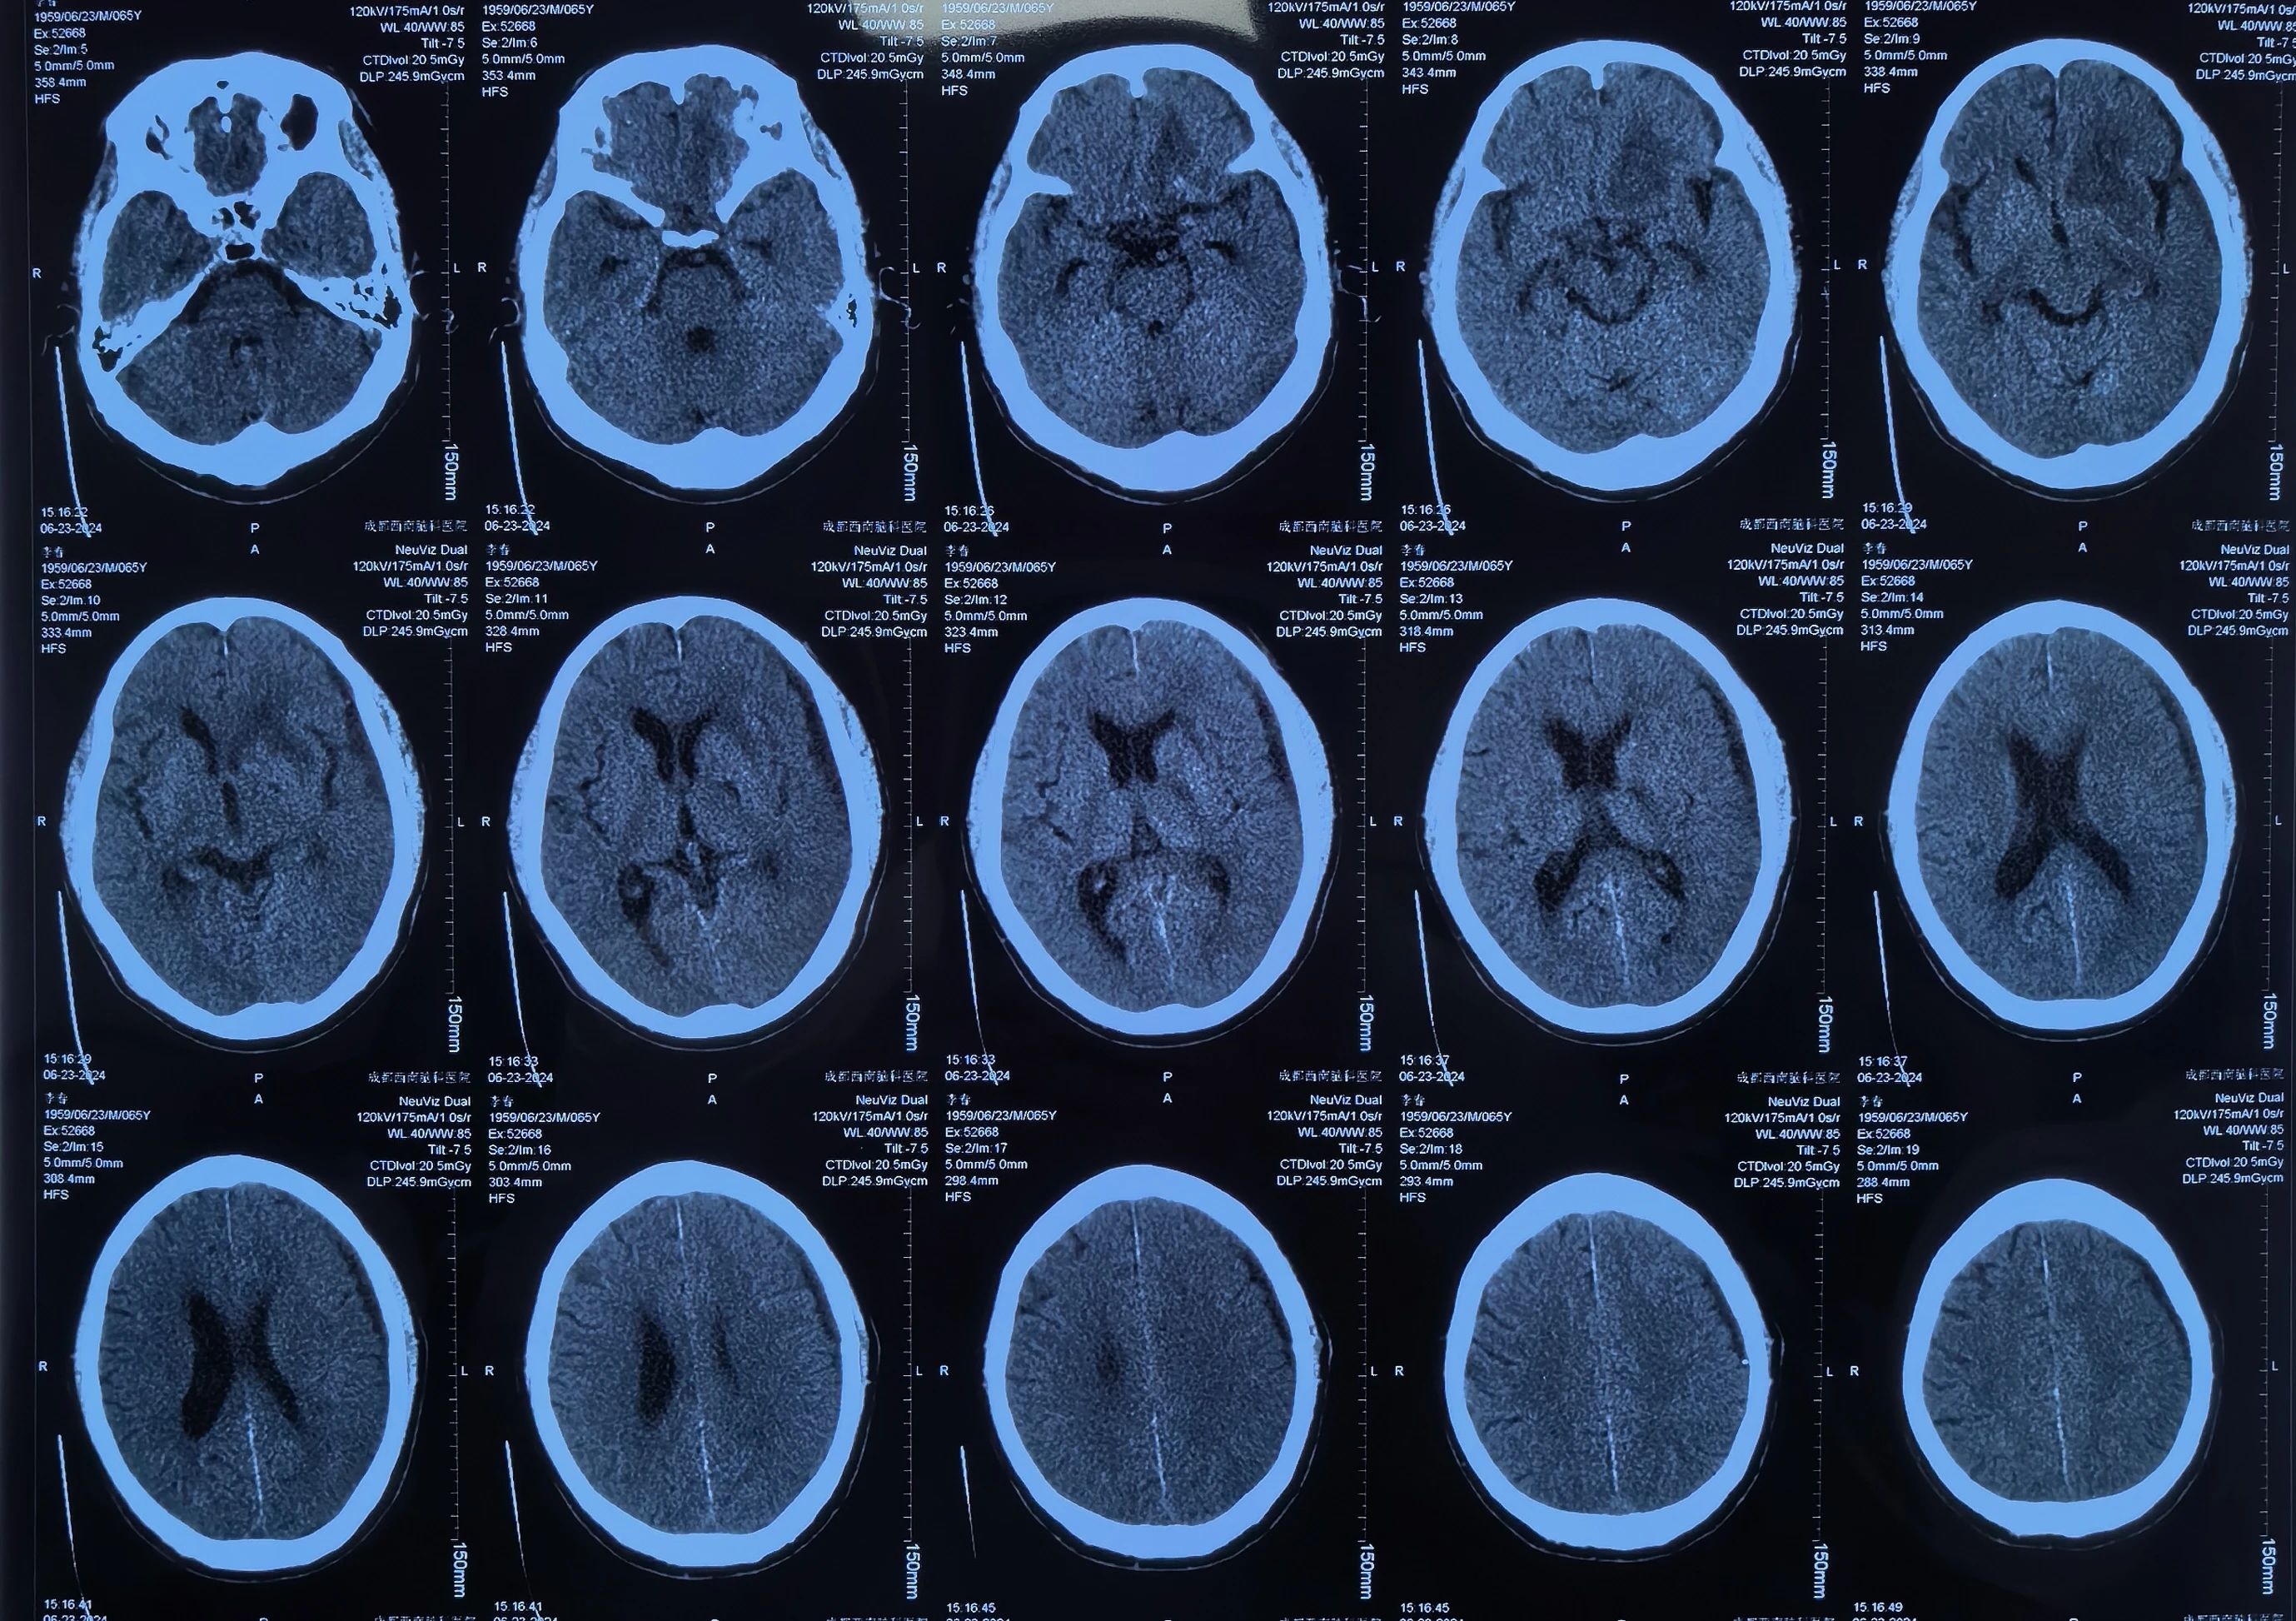

李先生术后引流中

术后李先生自觉头痛明显减轻,术后第三天复查头颅CT提示:硬膜下血肿基本清除,脑移位恢复正常。